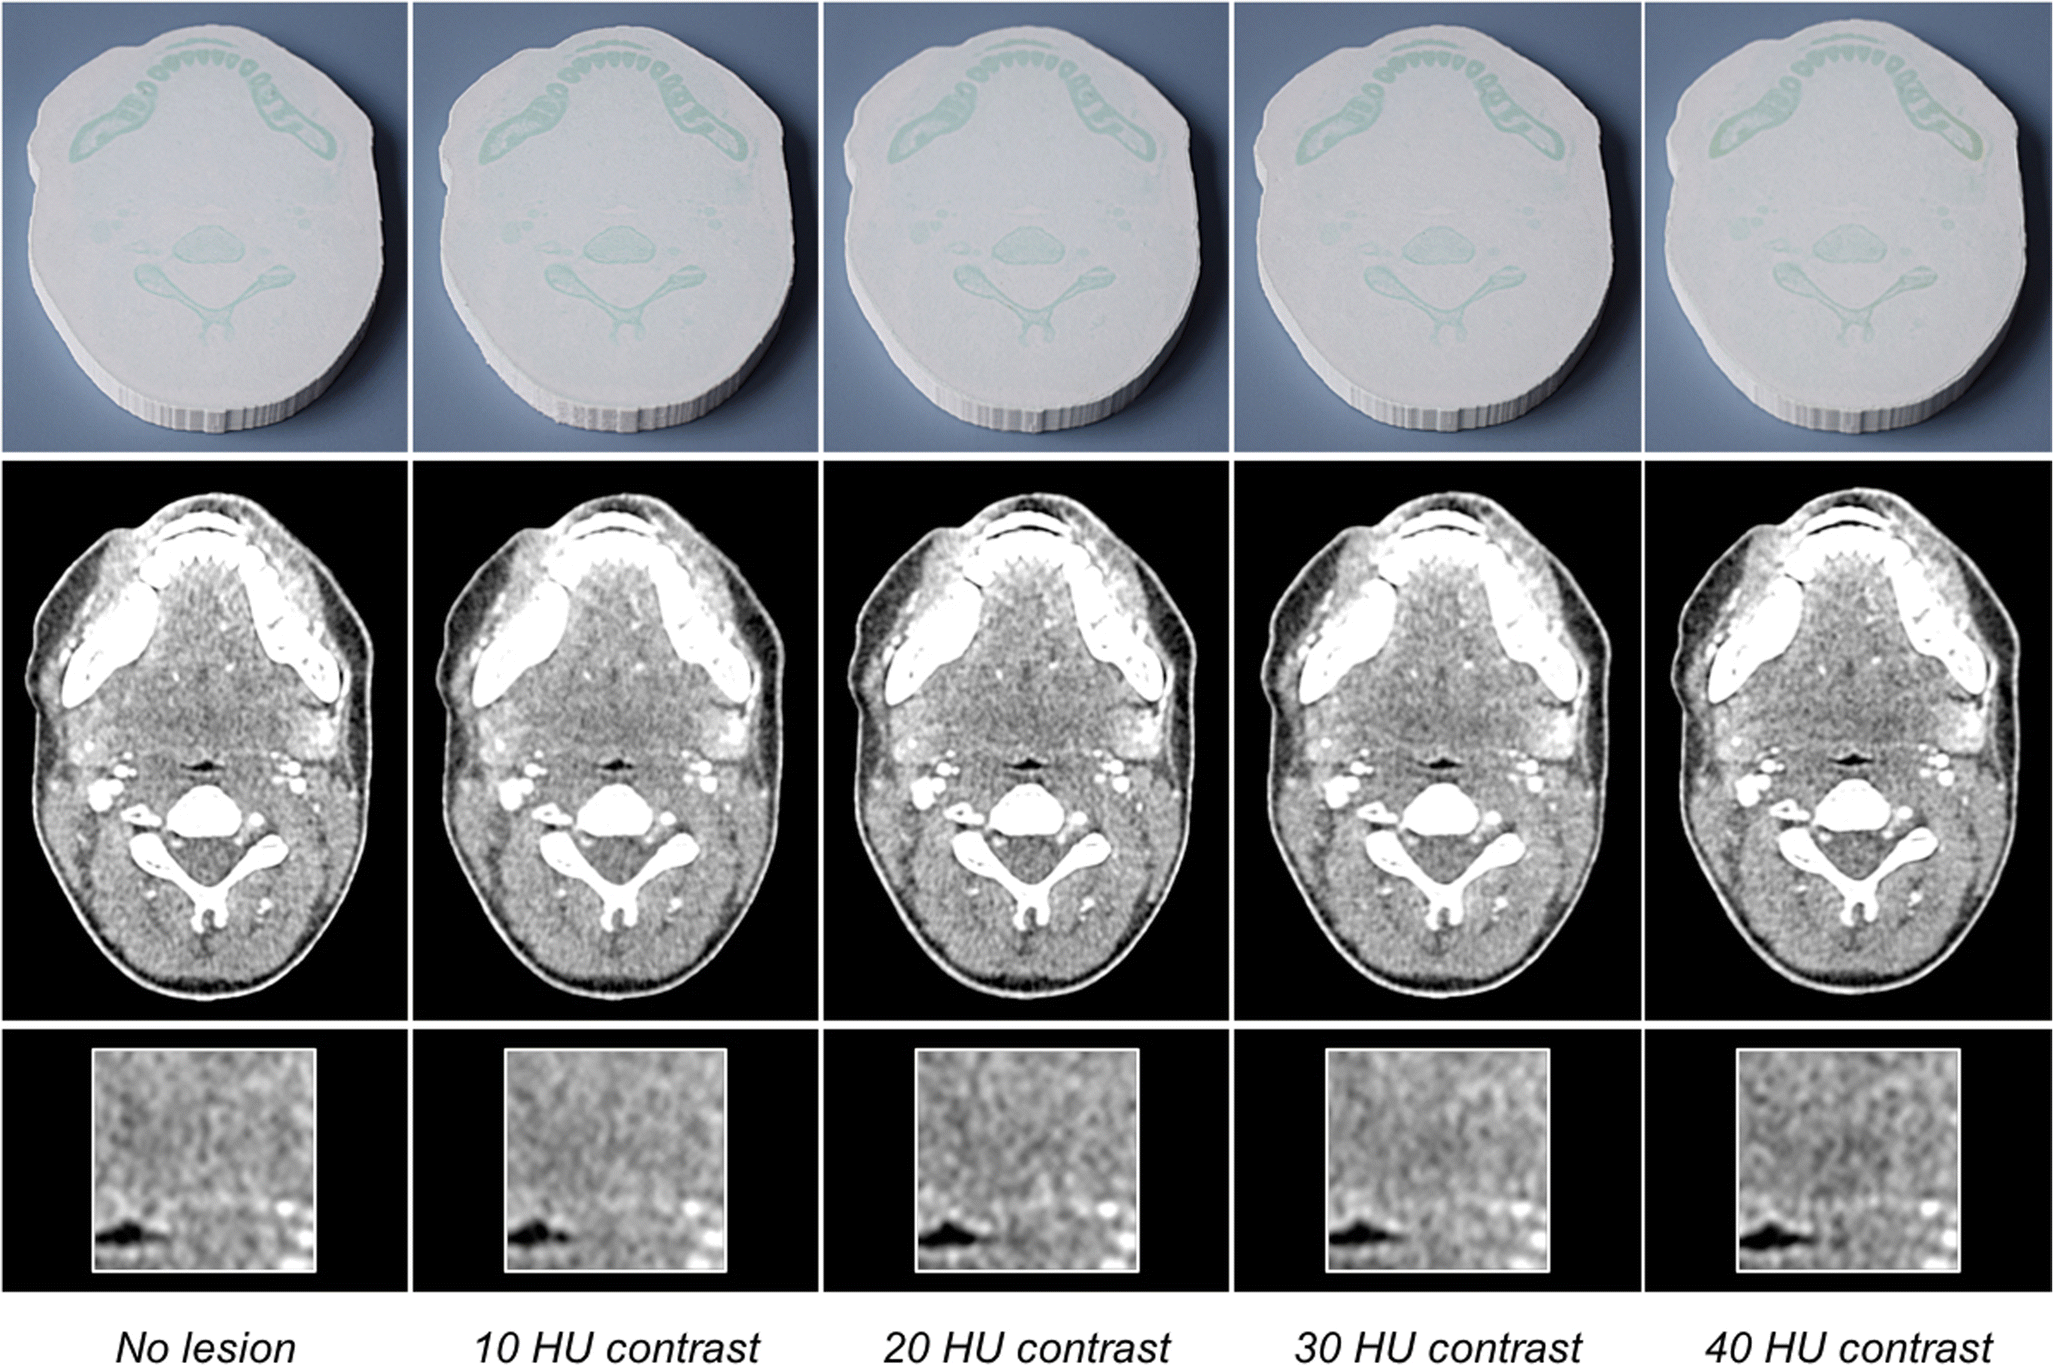

Figure 3 shows photographs and CT images of the phantoms and the original patient. All images are displayed with window level 40 and window width 350. The phantoms reproduced the size and the shape of the patient (mean ± SD phantom area 130.9 ± 0.1 cm2 vs. 131 cm2 for the patient).

Fig. 3

Photographs and CT images of the phantoms. The bottom row shows magnified details of the lesions in the left parapharyngeal space. All images are displayed with window level 40 and window width 350